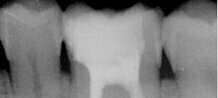

Cas clinique : Traitements endodontiques Dr Grunberg - dentiste à Paris 75012